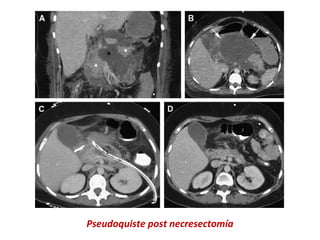

Pseudoquiste post necresectomía